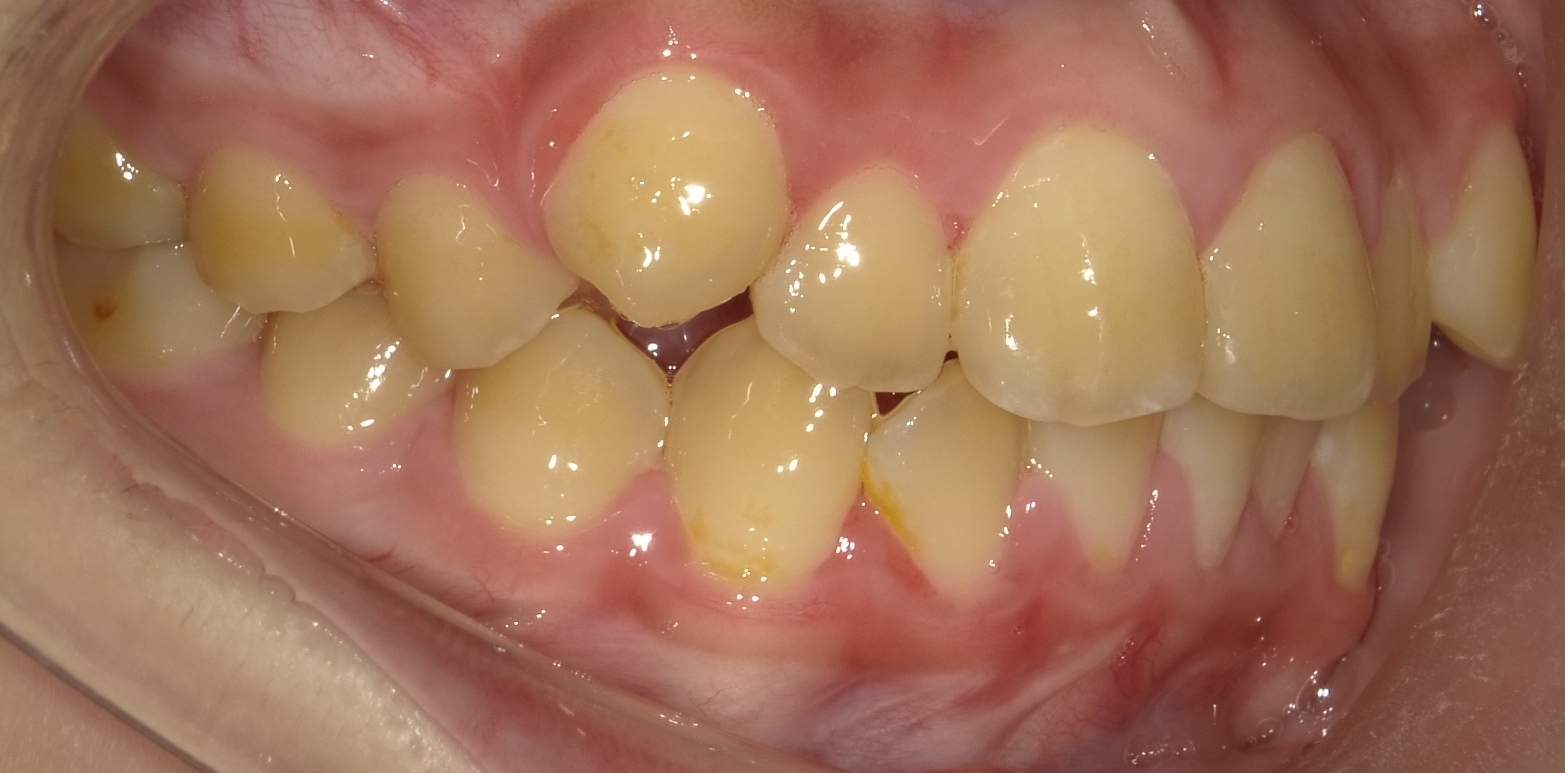

画像のような場合ですが抜歯をしないとあごの中に歯が

収まりきりません。

上下とも重なりが認められます。